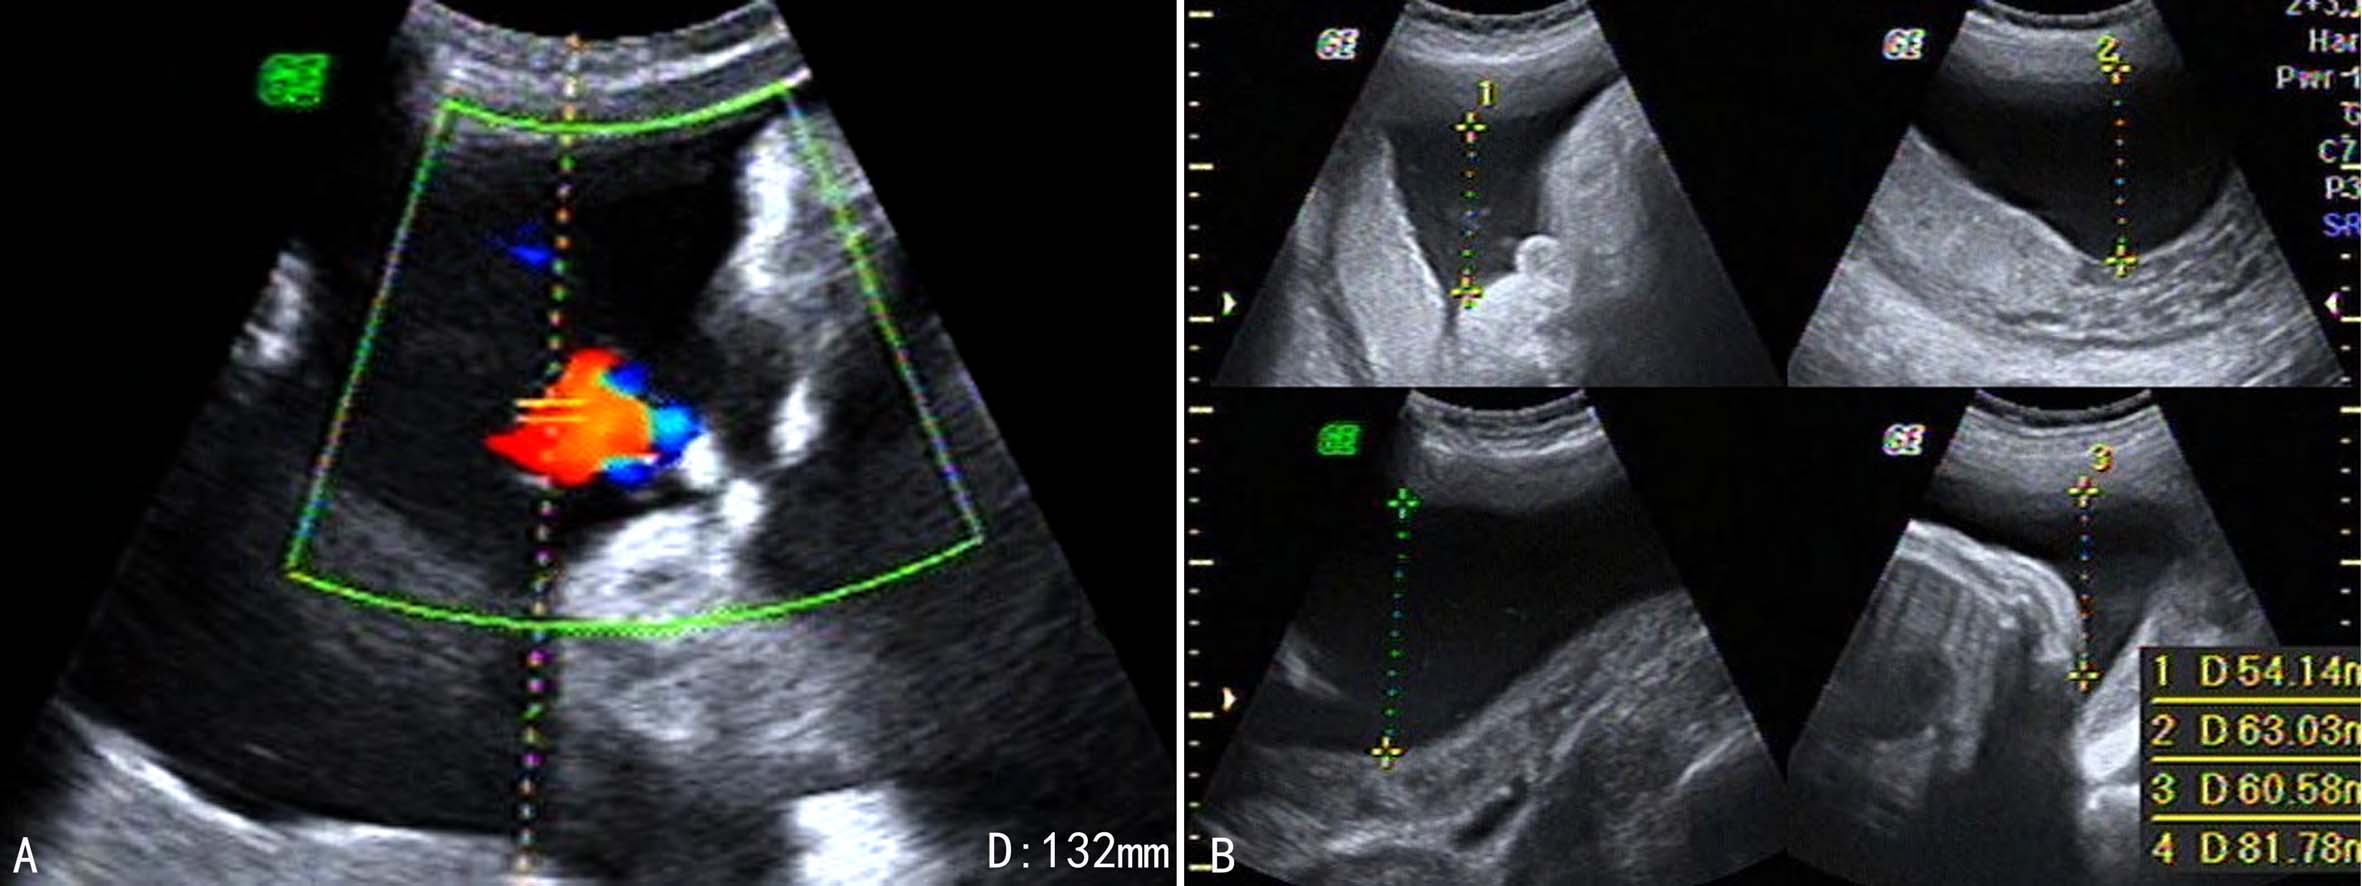

2.羊水池测量 测量方法同上。当羊水池不包含有胎儿肢体的最大无回声区内径>8cm时即应警惕有羊水过多,>10cm则肯定有羊水过多(图3A)。

3.羊水指数 测量方法同上。当羊水指数≥18cm时可考虑羊水过多(图3B)。

以AFI诊断羊水过多的界限值多集中在18cm、20cm、24cm等。

根据羊水池深部及AFI可以对羊水过多进行分度。羊水池深度8~<12cm、AFI 25~30时为轻度羊水过多,羊水池深度12~<16cm、AFI 30.1~35cm时为中度羊水过多,羊水池深度>16cm以上、AFI>35.1cm时为重度羊水过多。

图3羊水过多声像图